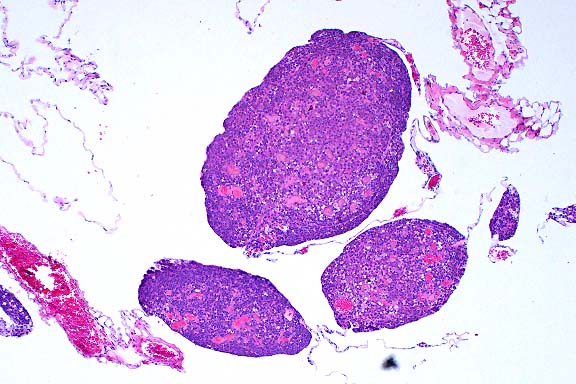

- Case 16-2. Lung. Interlobular septa are markedly expanded

by edema fluid.

- In the tissue section of this experimentally infected animal,

the pulmonary parenchyma is multifocally atelectatic, and the

interlobular septa and subpleural spaces are moderately to severely

expanded by edema and very mild inflammation (lymphocytes, plasma

cells, and neutrophils). Small to medium-sized arterioles throughout

the tissue are lined by endothelium in which the nuclei are prominent

and rounded, are darkly basophilic, bulge into the vascular lumina,

and contain darkly amphophilic viral inclusion bodies. Many of

these arterioles contain sloughed luminal endothelial cells admixed

with moderate numbers of mononuclear and polymorphonuclear cells,

and in some of the arterioles, inflammation extends into the

vessel wall where it is admixed with rare, brightly eosinophilic

hyalinized material (fibrinoid necrosis). Throughout the remaining

parenchyma there is multifocal atelectasis, alveolar capillaries

are expanded by neutrophils, and there is expansion of alveolar

septa by moderate numbers of neutrophils and lymphocytes. Transmission

electron microscopy demonstrated endothelial cell necrosis in

the lungs and alimentary tract and adenovirus particles in the

nuclei with protein crystalline arrays.

- Case 16-2. Lung. The pulmonary arteriole (20x view)

is expanded by lymphocytes and plasma cells. The endothelium

(both views) is lined by piled up, hypertrophic, endothelial

cells which rarely bear smudgy amphophilic intranuclear inclusions

(arrow head).

- AFIP Diagnosis: Lung: Endothelial degeneration and

hypertrophy, diffuse, with multifocal vasculitis, interstitial

pneumonia, diffuse edema, and endothelial intranuclear inclusion

bodies, black-tailed deer (Odocoileus hemionus columbianus),

cervid.

Note: A fat embolus was observed in some sections.